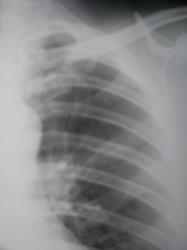

Линейная томография в прямой проекции через 1 см.